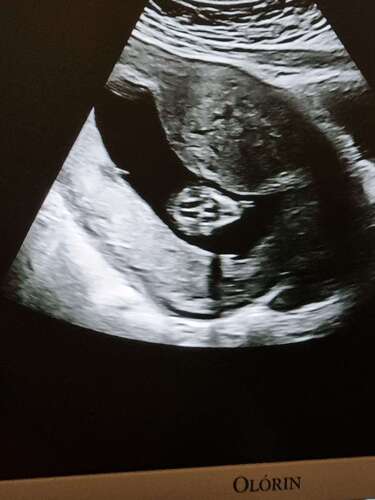

Hier zie je bovenin mijn myoom. Hij ligt voor de uitgang van m'n baarmoedermond. Bij de 20 weken echo zal moeten blijken of hij verder groeit en de uitgang zal versperren. Ik vind het allemaal wel een eng idee. Als dit laatste het geval is zal ik een keizersnee moeten.... iemand ervaring hiermee?